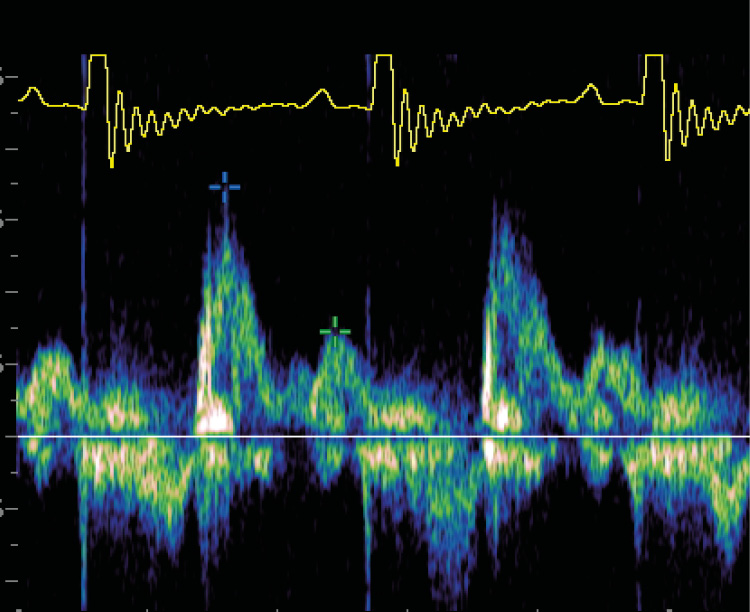

Seis horas después, se normaliza la frecuencia respiratoria, el paciente tolera agua y comida y se comprueban la disminución de las líneas B y la desaparición del patrón intersticial. La presión arterial sistólica se mantiene en 195 mmHg. El electrocardiograma muestra taquicardia sinusal, con una frecuencia media de 190-210 lpm (imagen 2).